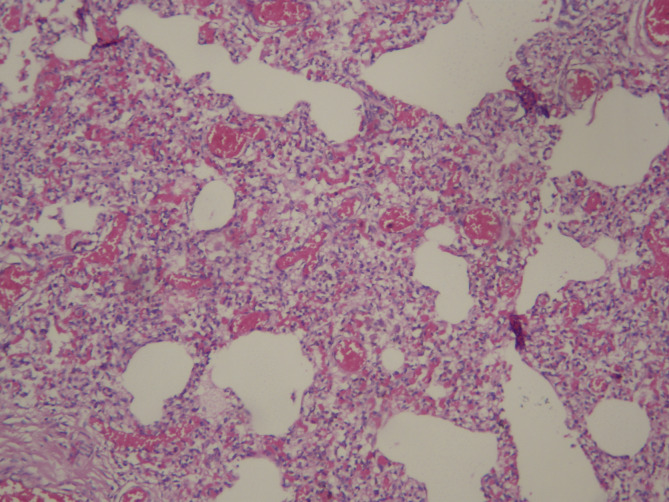

Fig. 2.

Interstitial pneumonia with prominent septal mononuclear inflammatory infiltrate (H&EX200).